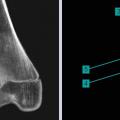

Exostose : saillie osseuse en continuité avec la corticale

EXOSTOSE

Tumeur à cellules géantes

TUMEUR A CELLULES GEANTES